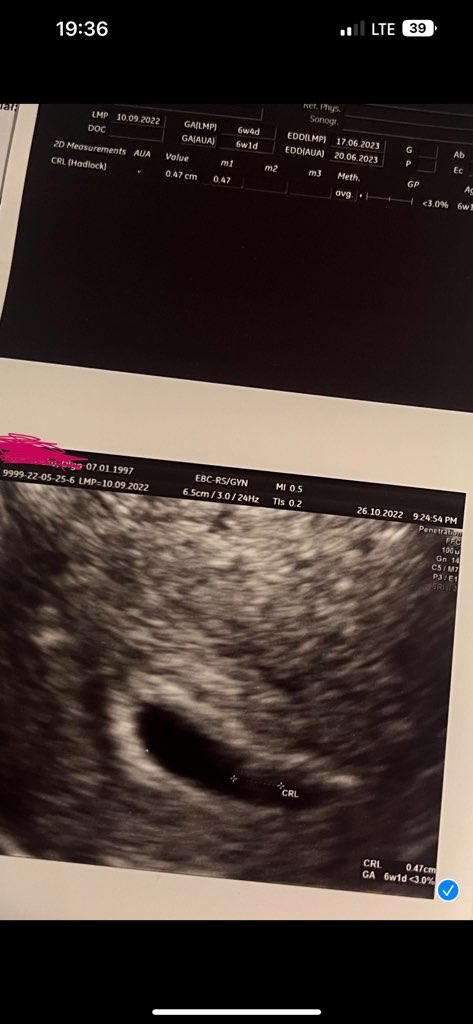

Jeśli masz możliwość, to zmień lekarzaDzięki bo trafiłam dzisiaj na lekarza mało miłego i powiedział mi że w sumie to ja w ciąży nie jestem ...